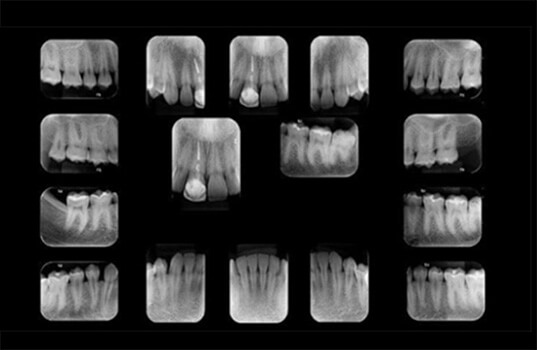

A Radiografia Periapical é um tipo de radiografia odontológica usada para avaliar a saúde do tecido dentário, incluindo a raiz do dente e a área à sua volta, conhecida como a área periapical. É uma ferramenta importante na avaliação de problemas dentários, como cáries, inflamações, infecções, fraturas e outros problemas da raiz do dente.

Na Radiografia Periapical, o paciente coloca a boca na máquina de Raio-X e precisa ficar parado por alguns segundos enquanto a máquina faz a imagem. A imagem resultante mostra a raiz do dente, a área periapical e outras estruturas circundantes, permitindo ao dentista avaliar a saúde do tecido dentário e identificar qualquer problema presente.